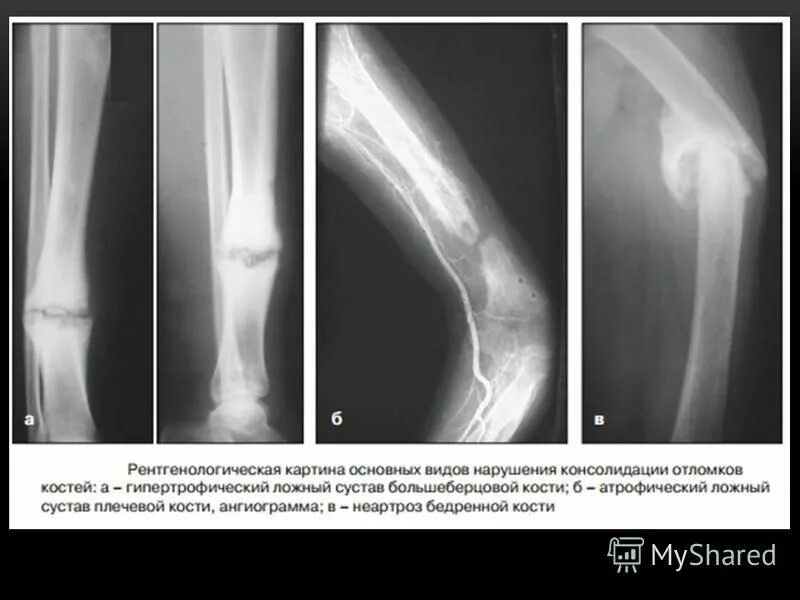

Не срастается сустав